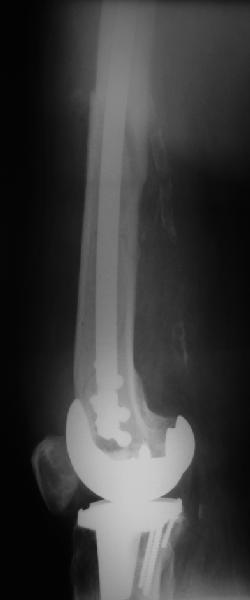

В приложении - недавний перипротезный перелом.

Имя     : 1get_image.jpg

Тип     : image/jpeg

Размер  : 10309 байтов

Описание: отсутствует

Url     : http://weborto.net:8080/pipermail/ortho/attachments/20110903/40f50831/attachment-0006.jpg